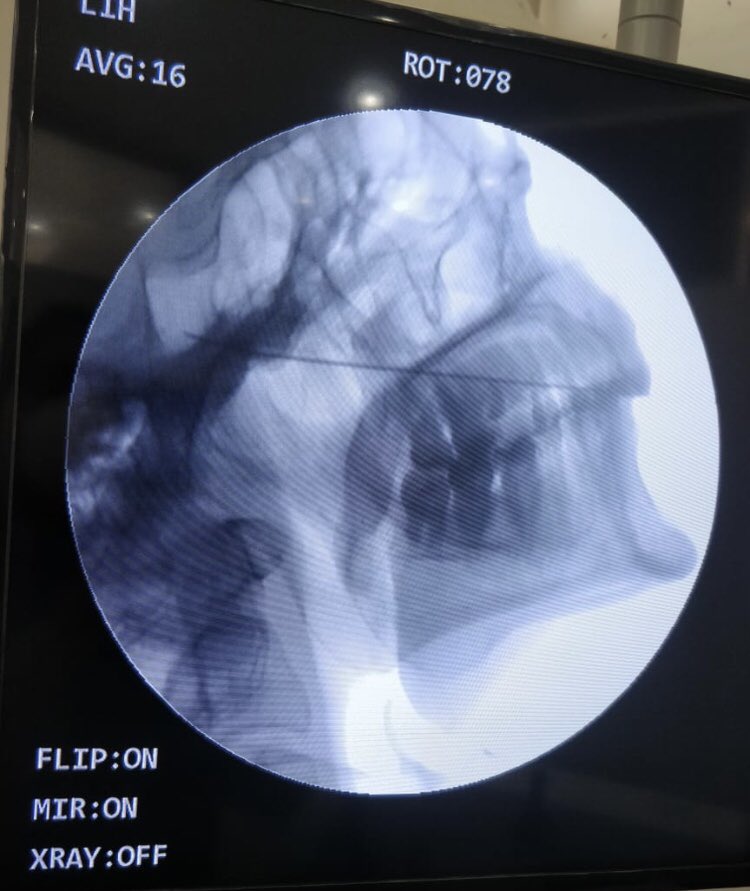

Radiofrequency procedure for #Trigeminal Neuralgia done just now at #Reliefpainservice kashmir. No sedation given. Pulsed RFA for 300 sec, before conventional RFA desensitises the ganglion for heated ablation (RFA). Patient did not require any sedation during the procedure.

tariqtramboo's tweet image. Radiofrequency procedure for #Trigeminal Neuralgia done just now at #Reliefpainservice kashmir.

No sedation given. Pulsed RFA for 300 sec, before conventional RFA desensitises the ganglion for heated ablation (RFA). Patient did not require any sedation during the procedure.